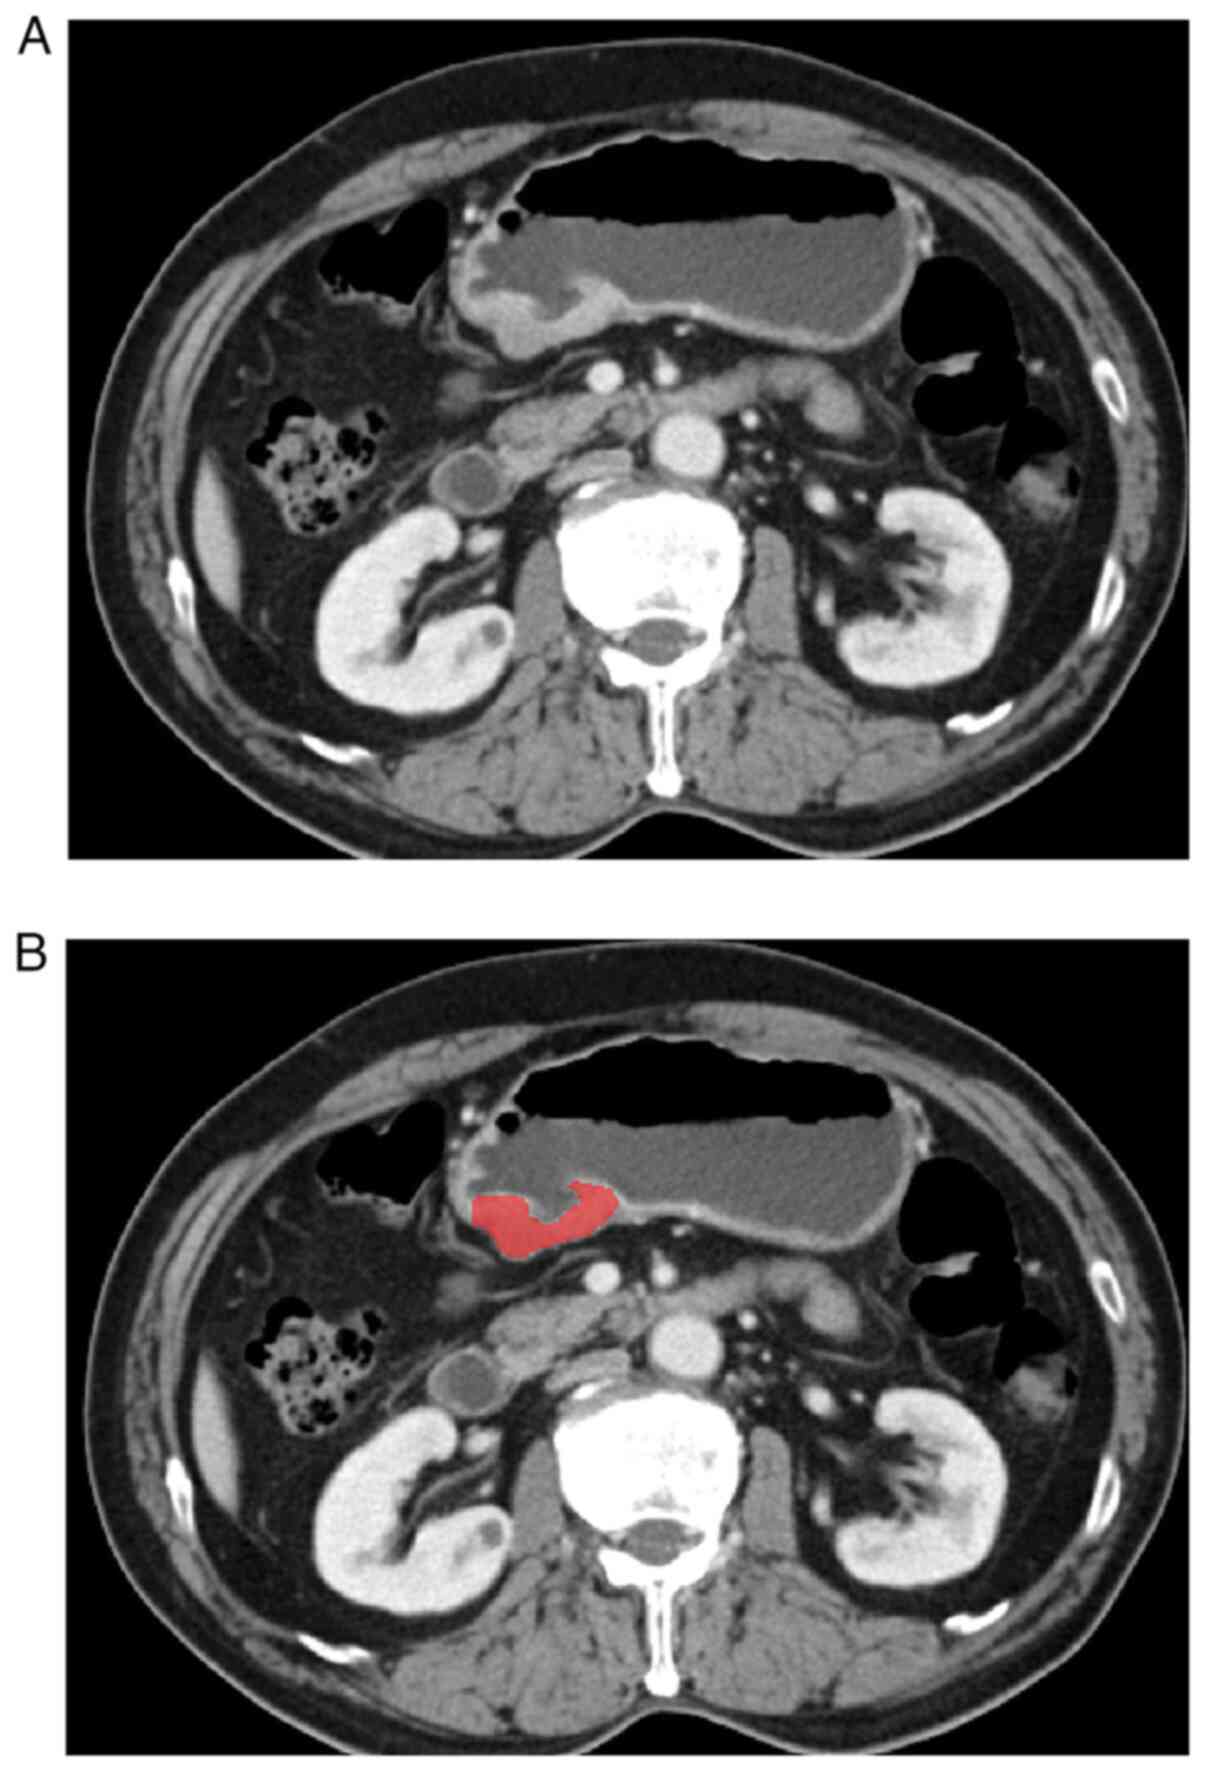

Tumor segmentation

The CT images of patients with gastric cancer were obtained from image storage and communication systems. Digital imaging and communications in medicine format portal phase images were used to delineate the lesions. Region of interest were delineated using ITK-SNAP (version 3.8.0, http://www.itksnap.org). In total, two radiologists with over 5 years of experience in diagnosing gastric diseases meticulously examined each patient's horizontal CT image and accurately delineated the tumor area layer by layer (Fig. 1). Observer 1 delineated the lesions of all patients with gastric cancer, and Observer 2 checked the accuracy of tumor delineation. If lesion segmentation was inconsistent between the two radiologists, a consensus was reached after consultation.

Figure 1

An example of segmentation lesion area in gastric cancer. (A) Localized thick wall of gastric cancer with enhancement is observed on the portal venous phase computed tomography image. (B) Manual segmentation on the same axial slice is depicted with red label.